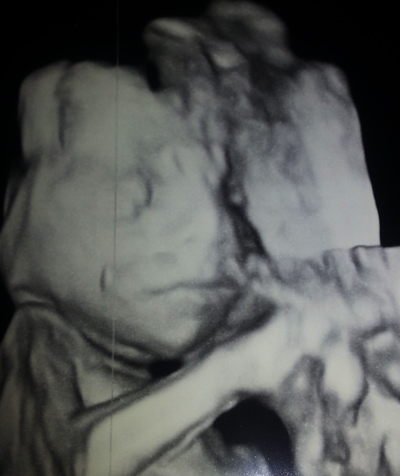

Nt-ultrassa nähtiin mielettömän vilkas vauva.

Vastasi viikkoja 11+5, pää-perämitan ollessa 4,85cm.

Niskaturvotus ja kaikki rakenteet normaalit.